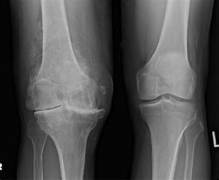

- 측정검사 : X-ray, MRI 등의 영상 촬영을 통해 관절의 상태를 확인합니다.

이러한 검사를 통해 골관절염의 진행 정도와 손상의 위치를 평가하여 적절한 진단을 내리게 됩니다.